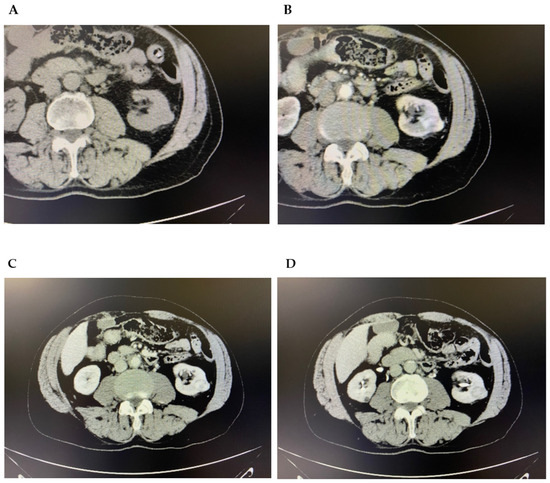

Case Report

Triple Synchronous Primary Malignant Tumors of the Liver, Kidney, and Lung in a Male Patient: Case Report and Systematic Review

by Alexandru Vlad Oprița, Eduard Achim, Cornelia Nițipir, Nicolae Boleac, Alissia-Nicoleta Pilatec and Florin Andrei Grama

Background: Triple primary malignant tumors (TPMTs) are extremely rare and represent a major diagnostic and therapeutic challenge. Their frequency has increased with advances in cancer detection and longer patient survival. Case presentation: We report the case of a 76-year-old male diagnosed with three [...] Read more.

Background: Triple primary malignant tumors (TPMTs) are extremely rare and represent a major diagnostic and therapeutic challenge. Their frequency has increased with advances in cancer detection and longer patient survival. Case presentation: We report the case of a 76-year-old male diagnosed with three synchronous primary malignancies involving the liver, left kidney, and right lung. Imaging revealed a hepatic mass with arterial enhancement and portal washout, a large left renal mass, and a cavitated pulmonary nodule. Histopathological and immunohistochemical evaluation confirmed three distinct tumors: well-differentiated hepatocellular carcinoma, chromophobe renal cell carcinoma, and invasive non-mucinous lung adenocarcinoma. A multidisciplinary oncology board recommended surgical resection of the liver and kidney lesions and stereotactic body radiotherapy for the lung tumor. The patient underwent hepatectomy and nephrectomy but experienced severe postoperative complications leading to multi-organ failure and death. Results of the systematic review: A systematic search identified 83 relevant cases of triple primary malignancies after full-text eligibility assessment. None of the 159 articles included after primary screening described a synchronous association of primary liver, kidney, and lung cancers. Conclusions: This case highlights the importance of thorough diagnostic assessment and individualized, multidisciplinary management in patients with multiple synchronous malignancies. To our knowledge, this is the first reported case of synchronous hepatocellular carcinoma, chromophobe renal cell carcinoma, and lung adenocarcinoma. Full article

(This article belongs to the Section Clinical Diagnosis and Prognosis)

Show Figures

Figure 1